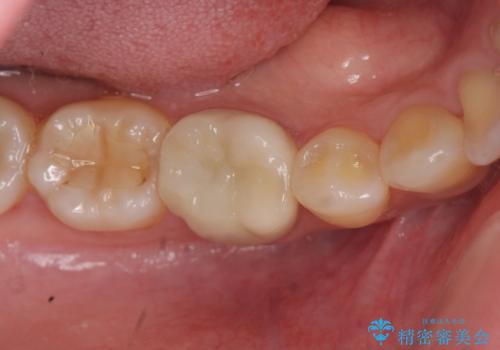

- 笑った際に見える銀歯を白くしたいと希望され来院されました。

銀歯の周囲にも虫歯が見られたのでインレーではなく、耐久性の強いフルジルコニアクラウンでの治療を計画します。

銀歯の周囲に虫歯が再発していたり、内部に虫歯が発生している場合などインレーからクラウン形態へとした方が長期的予後が良い場合があります。